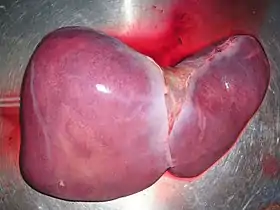

A healthy human liver removed at autopsy | |